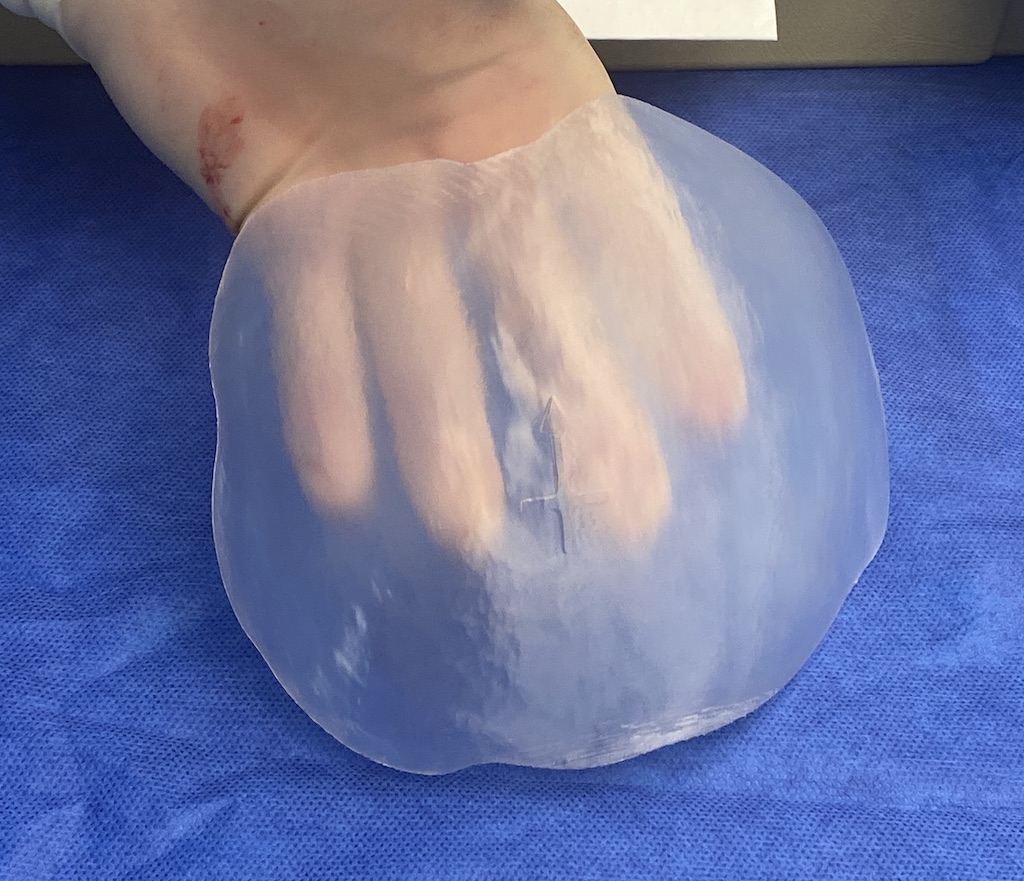

Scalp avulsion due to traumatic injury which left a large patch of non-hair bearing scalp.

Hair bearing scalp reconstruction using a first stage tissue expanders and second stage scalp scar removal.

Scalp avulsion due to traumatic injury which left a large patch of non-hair bearing scalp.

Hair bearing scalp reconstruction using a first stage tissue expanders and second stage scalp scar removal.